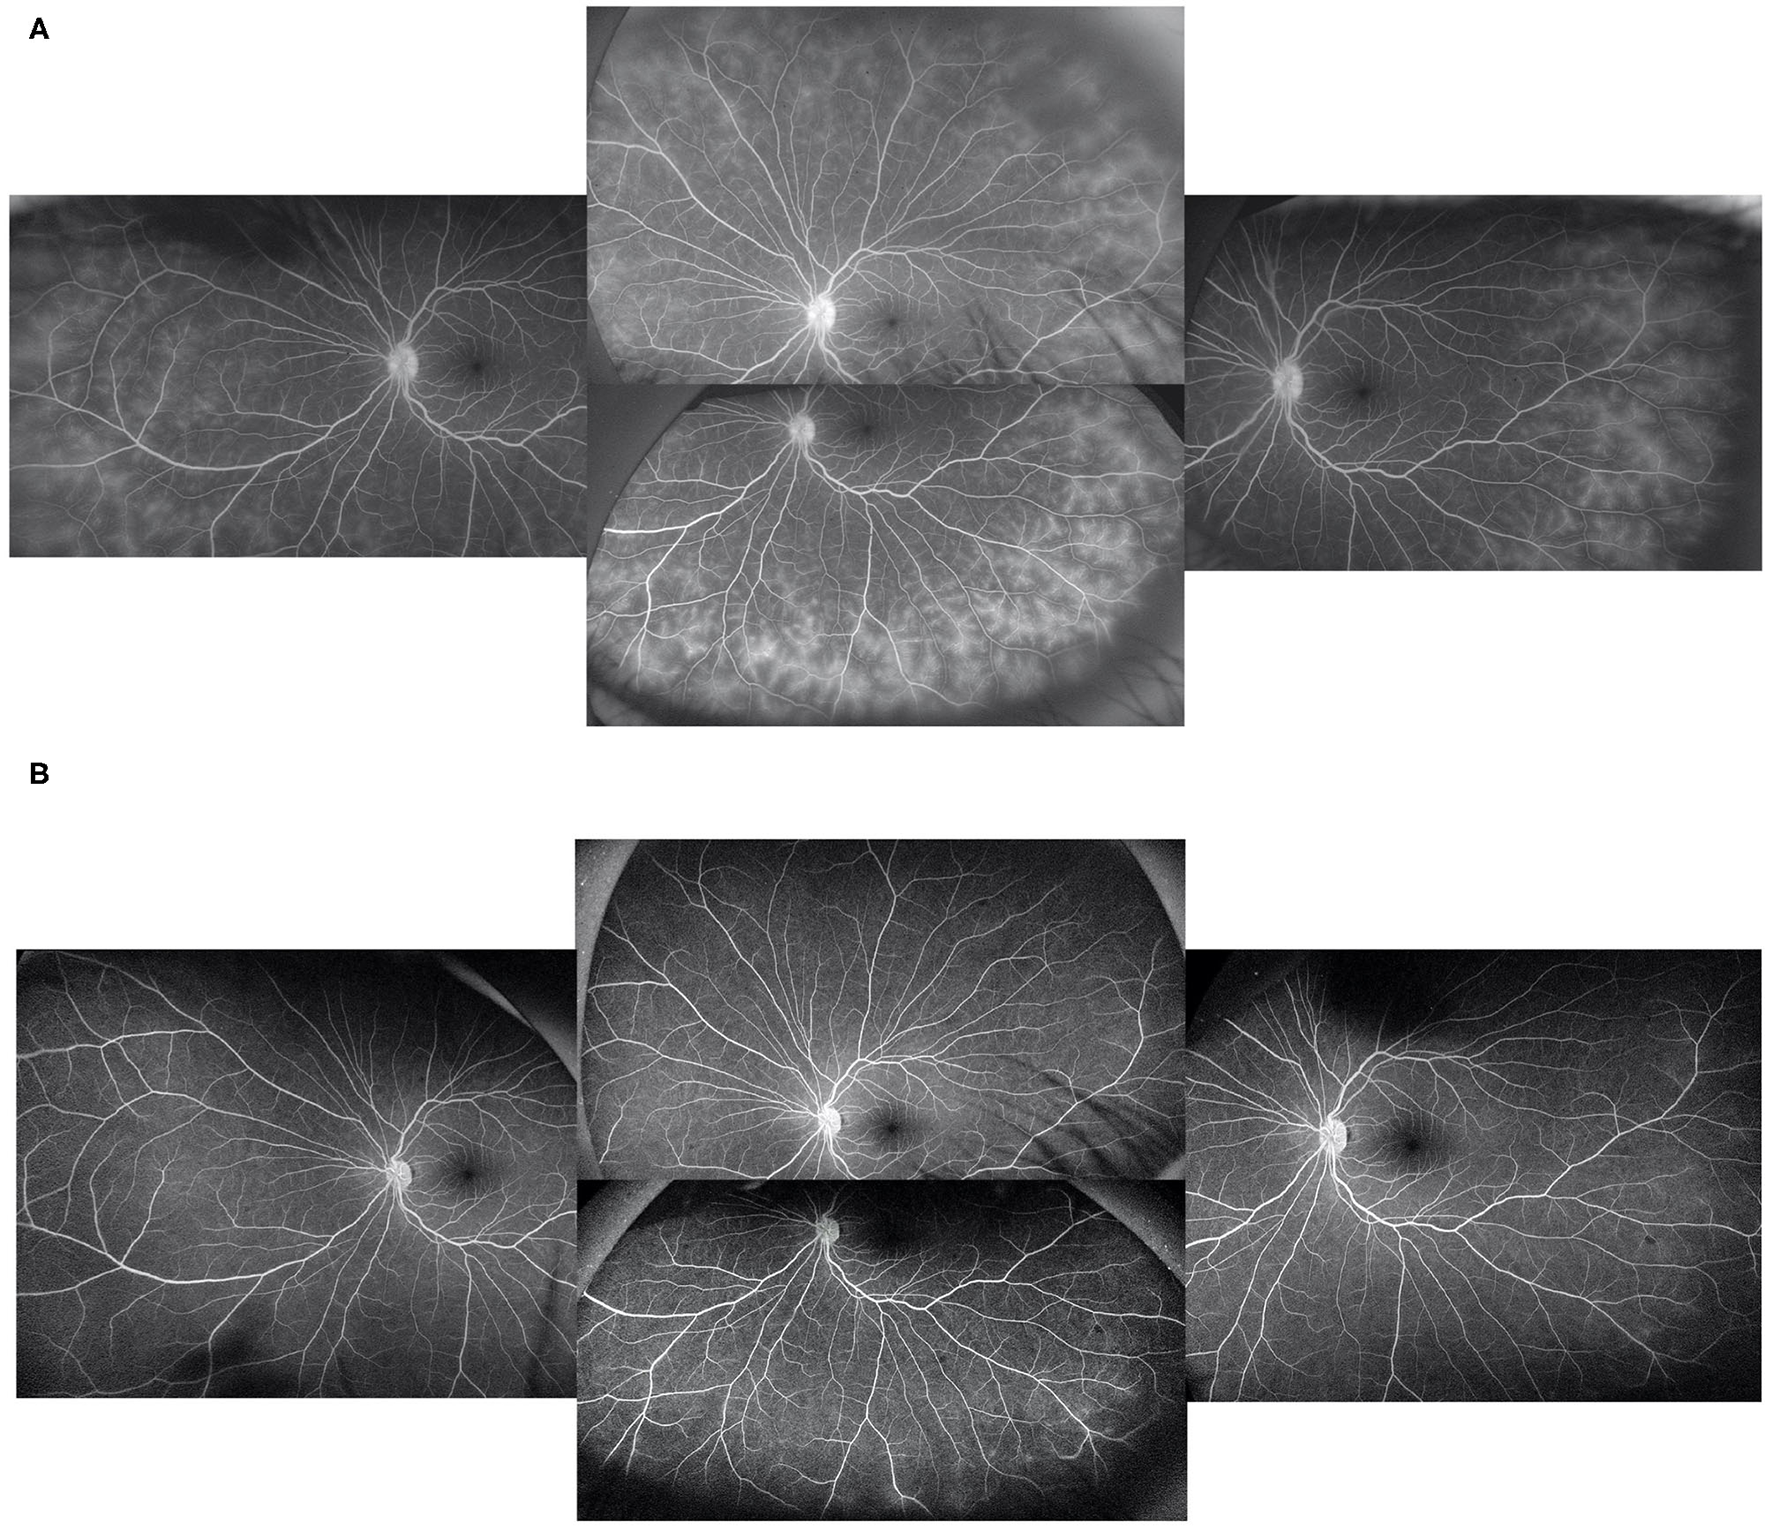

Basic information collected included patient demographics, uveitis etiologies, course of the disease, prior history of topical GC and systemic IMT treatments, and ocular complications due to prolonged inflammation. The primary outcome was the extent of vascular leakage on UWFFA. The secondary outcomes were BCVA, inflammatory parameters, such as fresh keratic precipitates, anterior chamber cells and vitreous cells, topical GC eye drop frequency, and IMT (i.e., oral GC and immunosuppressive drug) load. The dosing and interval of adalimumab and the adverse events of adalimumab were also recorded. Peripheral retinal vascular leakage is quantified based on the method developed by the Angiography Scoring for Uveitis Working Group (ASUWOG) (7), in which vascular leakage in each peripheral quadrant is scored 1 if limited and scored 2 if diffuse, as demonstrated by Figure 1. Vascular leakage was evaluated by two ophthalmologists (H. S. and JY. X.) and the average score was calculated for analysis. Relapse was defined as a two-step increase in anterior chamber cell grade or an increase from 3 to 4 according to SUN criteria (6). Visual acuity was transformed to the logarithm of the minimum angle of resolution (logMAR) for data analysis. Fresh keratic precipitate was recorded in a dichotomous method. The anterior chamber cells were recorded by the SUN criteria, which count the anterior chamber cells per 1-mm2 field on standard slit-lamp examination (6). The slit lamp was pushed forward to the vitreous for vitreous cell evaluation. The grading method was the same as the anterior chamber cell grading described by SUN. Systemic IMT load is assessed with a weighted semiquantitative scale for each medication, as presented in Table 1, to provide a combined, single numeric score for the systemic immunosuppression load according to a method by Nussenblatt et al. (8).

FIGURE 1

www.frontiersin.org

Figure 1. Demonstration of limited (A) and diffuse (B) vascular leakage.

At baseline, the ASUWOG score was 4 ± 3. Compared to baseline, the ASUWOG score decreased significantly at the 3-month follow-up visit to 2 ± 2 (2.87, 95% CI (2.14, 3.60), p < 0.001; Figure 2). For patients who had a complete remission of vascular leakage and had no inflammatory exacerbation on slit lamp examination during regular follow-ups, UWFFA was not performed. Thus, only ten children underwent the UWFFA at the 6-month follow-up visit, and the ASUWOG score demonstrated a decrease in these patients from 5 ± 3 at baseline to 3 ± 2 at 3 months and further decreased to 2 ± 2 at 6 months (2.75, 95% CI (1.76, 3.73), p < 0.001, 6 months vs. baseline). At the time of adalimumab application, fifteen eyes achieved inflammatory remission with six to eight times 1% prednisolone eye drops per day. The remaining 24 eyes achieved inflammatory control after 3 months of treatment. Ocular inflammation parameters, such as fresh keratic precipitates, anterior chamber cell, and vitreous cell, were improved significantly at the 3-month follow-up visit (p < 0.001, p < 0.001, p < 0.001; Table 3). There was a statistically significant difference in improvements in BCVA (p = 0.013, p = 0.005) and a reduction in topical GC eye drops (p < 0.001, p < 0.001) at the 3- and 6-month follow-up visits. The systemic immunosuppression load was also reduced gradually but only showed a significant difference compared with baseline at 6 months (p = 0.404 for 3 months, p = 0.014 for 6 months; Table 4). All these parameters further improved at the additional last follow-up visit if available (Tables 3, 4).

FIGURE 2

Figure 2. In a patient with peripheral vascular leakage at baseline (A), 3 months of adalimumab treatment led to complete alleviation of vascular leakage (B).

As expected, vascular leakage, represented by the ASUWOG score, is reduced dramatically upon the addition of adalimumab, which is intuitively demonstrated in Figure 2. Apparently, the reduction in vascular leakage on UWFFA was in parallel with other traditional measurements of disease activity. However, when we tried to perform a correlation test to demonstrate this association, we did not obtain a definite result (data not shown), as expected. The reason might come from three aspects. One was that the change in the traditionally measured inflammatory parameters was similar in each individual, but the change in the extent of vascular leakage was of a wider range. Thus, a statistically significant correlation was hard to determine. Another aspect might be caused by the time interval between the traditional inflammatory parameter data collection and the performance of UWFFA. In the real clinical setting, potential candidates for adalimumab application would undergo UWFFA screening first, and further blood test results or X-ray were needed before the application of adalimumab, when the other inflammatory parameters were collected. Third, for ethical concerns, if retinal vascular leakage healed without relapse of anterior chamber inflammation, UWFFA at 6 months was not performed. Thus, data were limited to fully demonstrate the correlations between peripheral retinal vascular leakage and the other inflammatory parameters. Due to these concerns, we still held a positive view that peripheral vascular leakage on UWFFA might serve as an indicator of disease activity and be useful for disease monitoring in pediatric anterior uveitis.